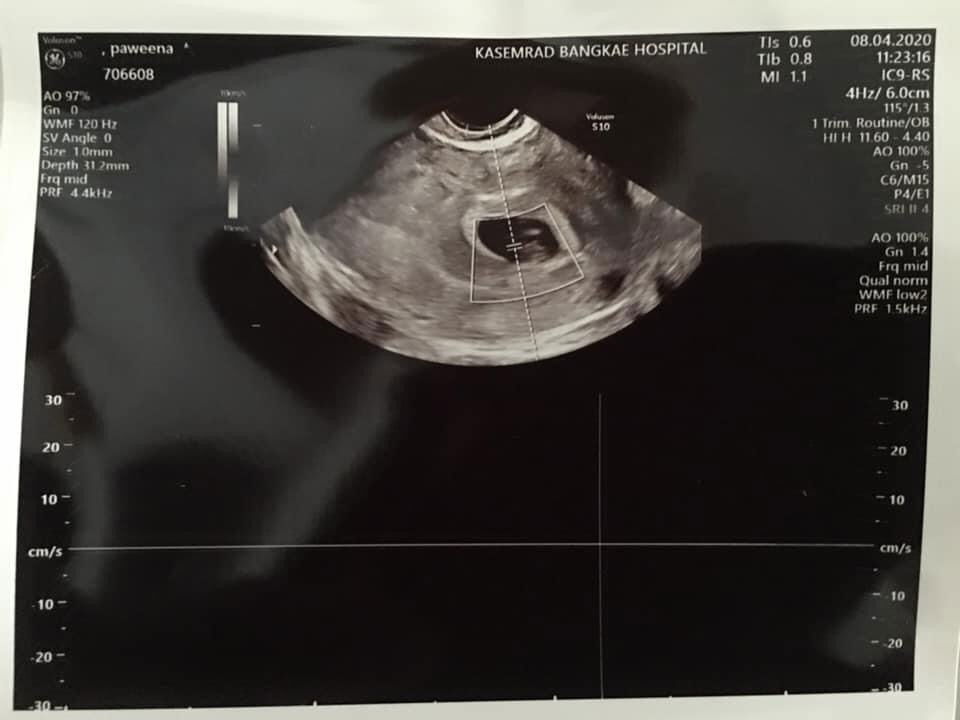

เมื่อวันจันทร์ที่ผ่านมา เรามาเลือดออกนิดหน่อยคะแค่เปื้อนๆ สีน้ำตาลเลยไม่เอะใจ วันอังคารไปทำงานต่อ ช่วงเย็นกลับมามีเลือดออกเป็นลิ่มนิดเดียวสีน้ำตาลเหมือนเดิม เช้าวันพุธเราเลยไป รพ.เล่าอาการให้คุณหมอฟัง คุณหมอให้อัลตร้าซาวด์ปรากฎว่าน้องไม่อยู่แล้วค่ะ เสียใจมากท้องแรกด้วย อยากเตือนคุณแม่ถ้ามีเลือดออกเป็นอาการที่ไม่ปกตินะคะ ต้องหาหมอโดยด่วยที่สุดค่ะ